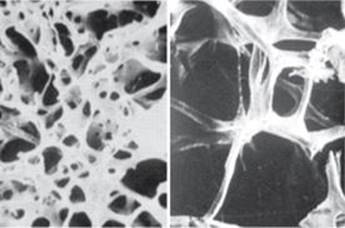

On the other hand, osteoporosis is caused by a relative excess of osteoclastic function. Loss of bone matrix in this condition (Figure 21–11) is marked, and the incidence of fractures is increased. Fractures are particularly common in the distal forearm (Colles fracture), vertebral body, and hip. All of these areas have a high content of trabecular bone, and because trabecular bone is more active metabolically, it is lost more rapidly. Fractures of the vertebrae with compression cause kyphosis, with the production of a typical “widow’s hump” that is common in elderly women with osteoporosis. Fractures of the hip in elderly individuals are associated with a mortality rate of 12–20%, and half of those who survive require prolonged expensive care.

FIGURE 21–11 Normal trabecular bone (left) compared with trabecular bone from a patient with osteoporosis (right). The loss of mass in osteoporosis leaves bones more susceptible to breakage.